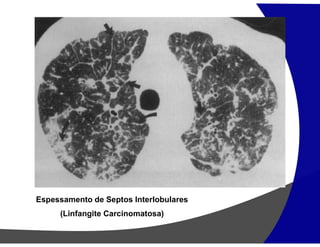

Espessamento de Septos Interlobulares

(Linfangite Carcinomatosa)

Espessamento dos septos interlobulares

Linfangite Carcinomatosa

• Espessamento irregular ou nodular

• Espessamento dos feixes broncovasculares

• Distribuição não dependente do decúbito